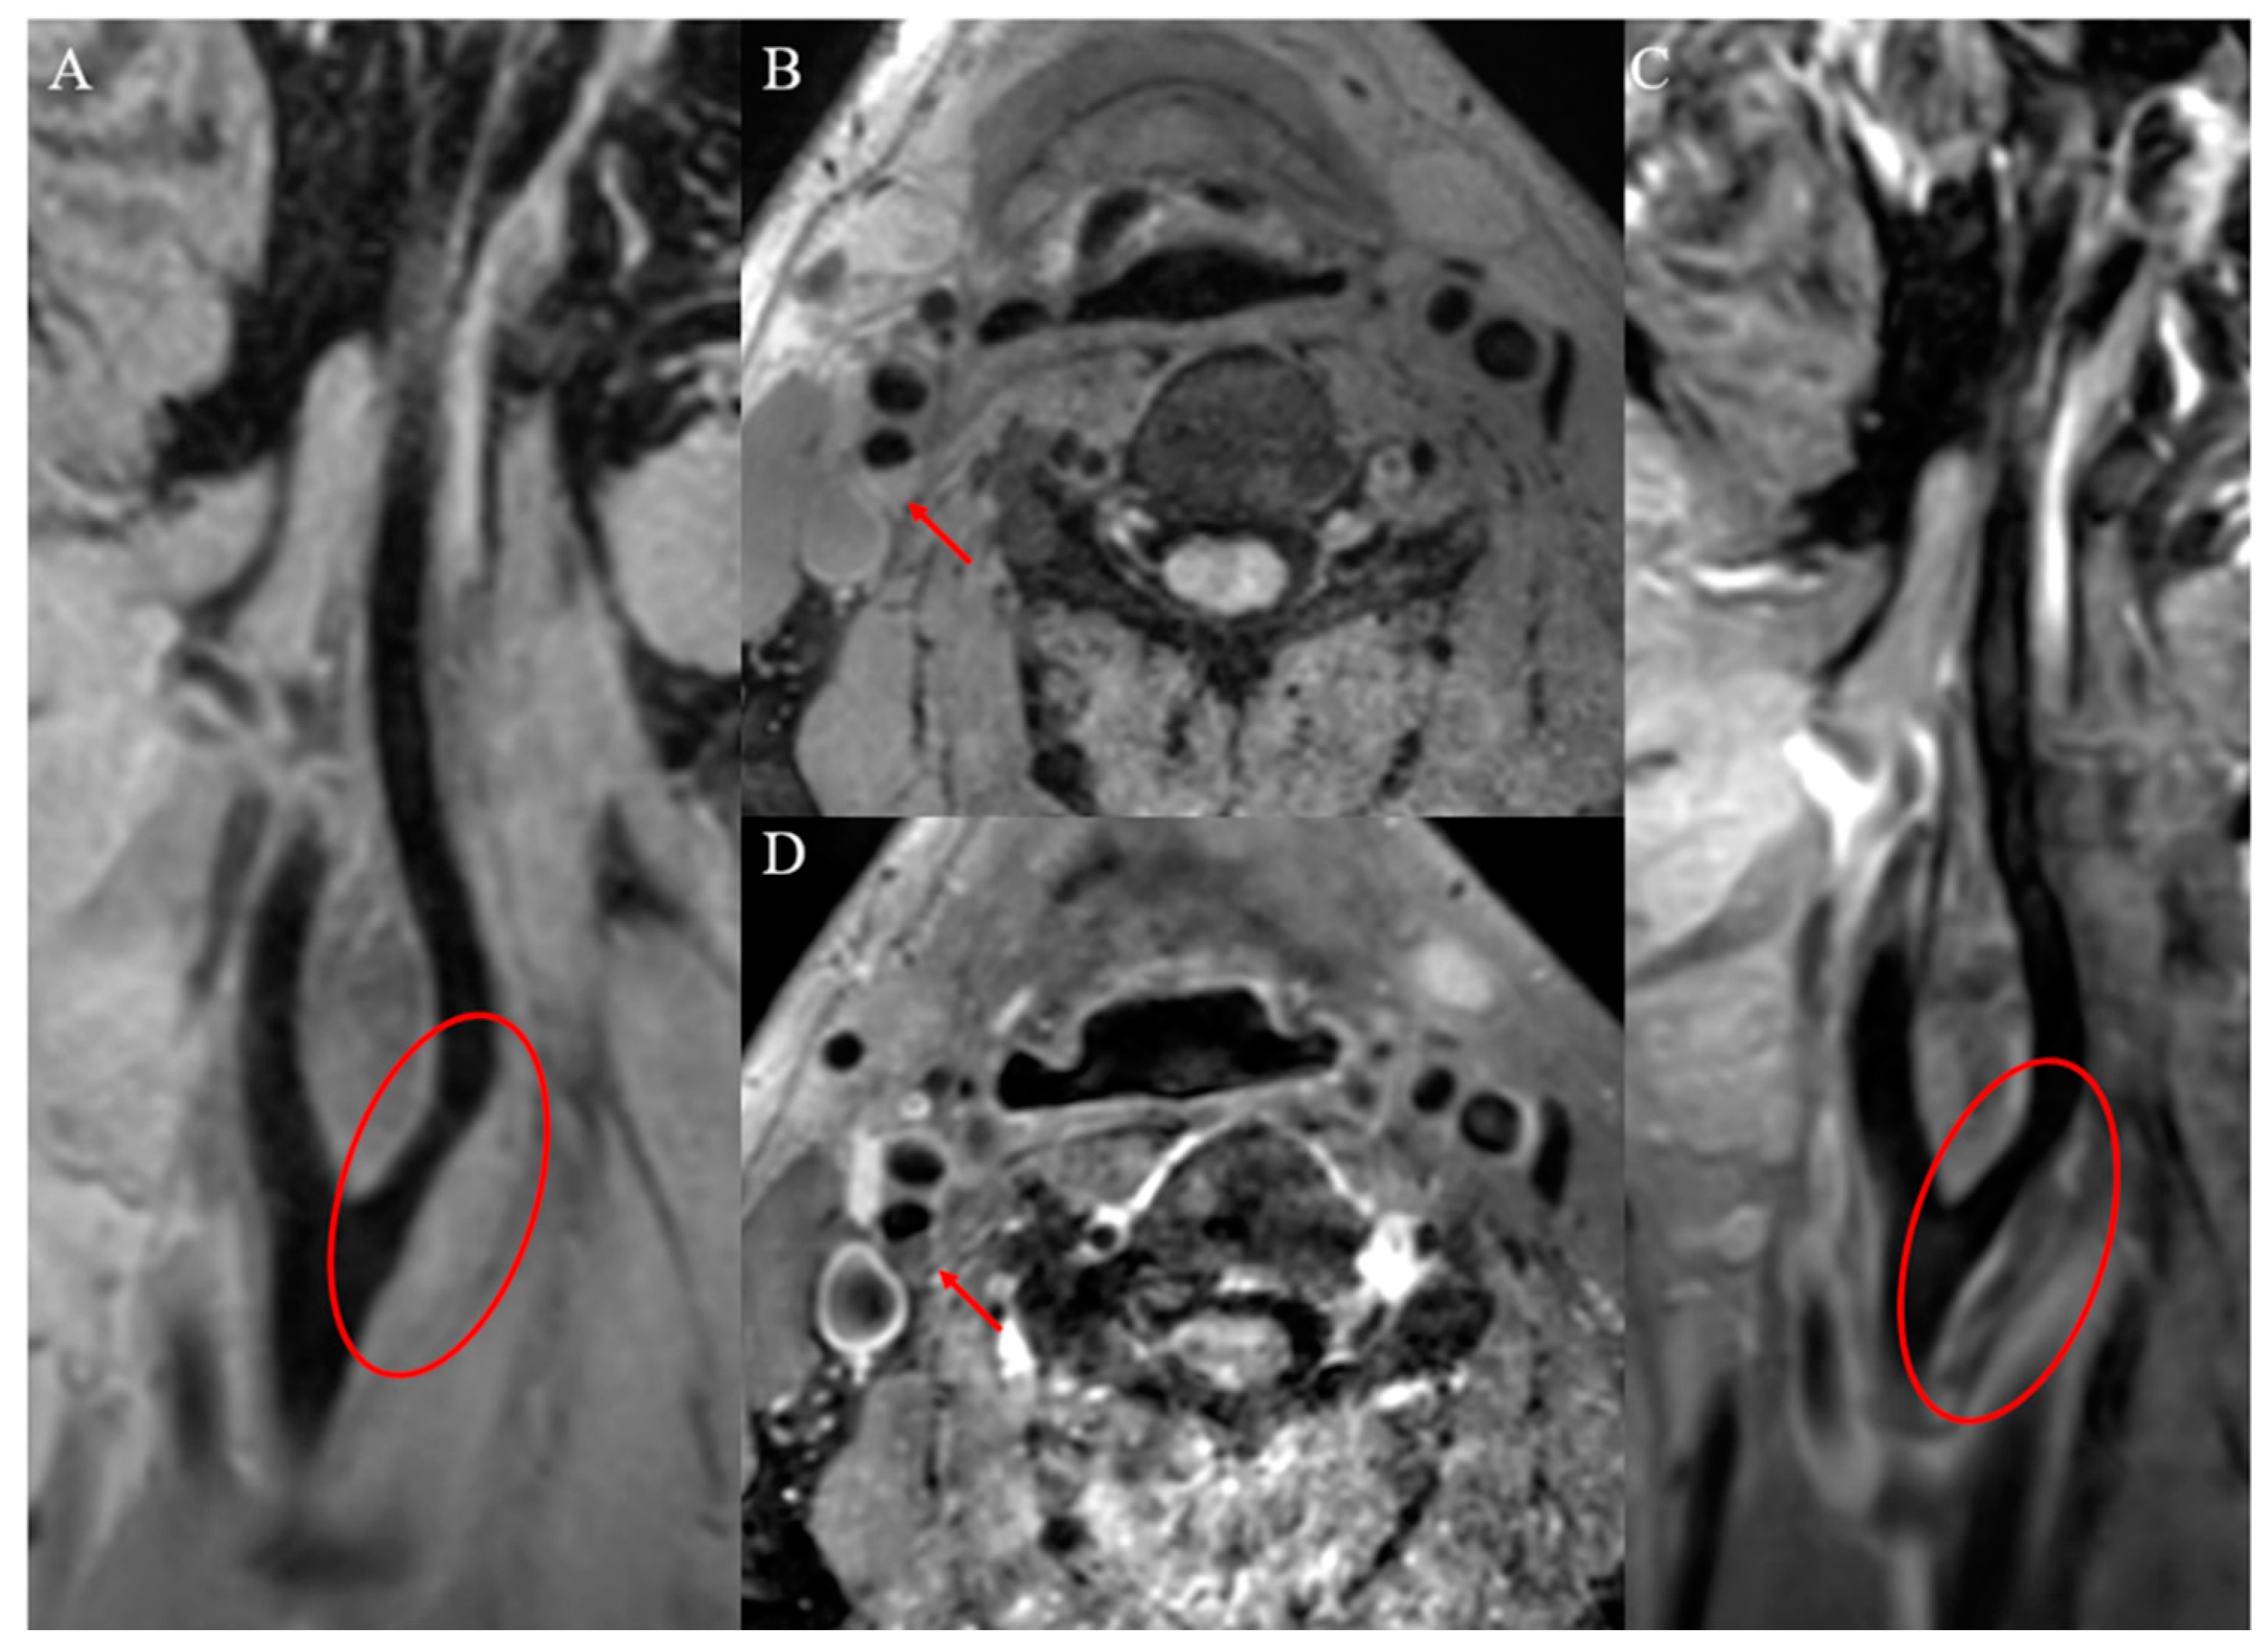

2.1.4. Plaque Surface Ulceration

2.1.5. Positive Vascular Remodeling